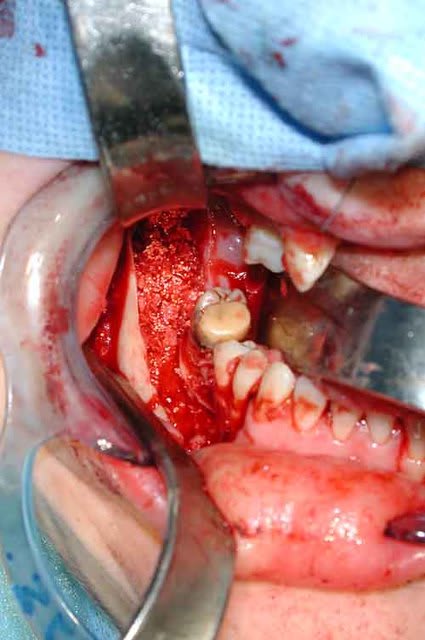

Bref, en ce qui concerne ce cas (assez récent), je vous livre le raisonnement qui a été le notre : probables kystes péricoronnaires sur les dents incluses (il n'y a pas de dents "surnuméraires"...). Décision d'abord chirurgical pour énucléation des 3 kystes (les ponctions ne "marchent" pas dans ces lésions) et examens anatomopathologiques extemporanés pour décider, en per-opératoire, de la conduite à tenir (photo 1).

Diagnotic extemporané : kératokystes (!). Les dents incluses se sont donc avérées être un piège diagnostic! Le traitement s'est de ce fait contenté d'un curetage appuyé des paroies osseuses, conservation des 2 nerfs dentaires et, en raison de la taille des kystes mandibulaires et du risque de fracture post-opératoire, nous avons y avons associé une greffe (hydroxyapatite + os autologue (crête illiaque) + PRP) au niveau mandibulaire uniquement (photos 2 et 3)et blocage intremaxillaire pendant 15 jours.